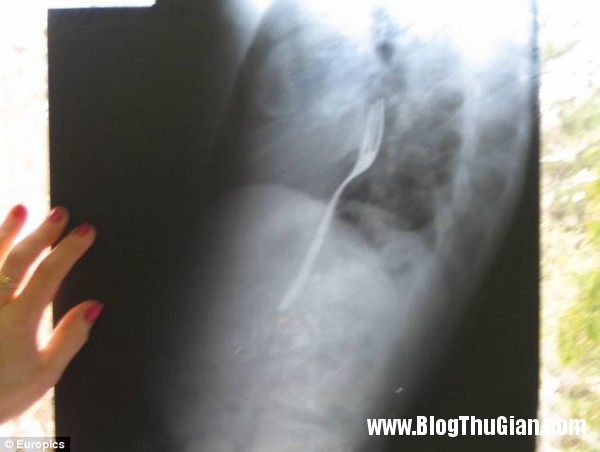

Hình chụp X-quang chiếc dĩa mắc trong cổ họng anh Radu.

Kết quả chụp X-quang cho thấy có một chiếc dĩa kim loại mắc kẹt ở thực quản. Anh Radu cũng thành thật thừa nhận nguyên nhân mắc kẹt với bác sĩ.